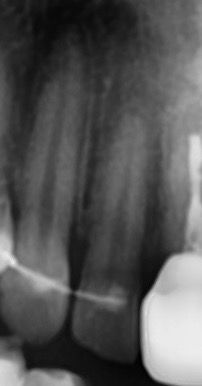

치과에서 파노라마 , 치근단사진 , 씨티 를 함께 찍었고

앞니 뿌리끝 염증이 의심되어 씨티 확인해보니

염증은 없다는 소견을 받았습니다

치과에서는 까맣게 보이는게 뼈의 밀도 차이라고 하셨는데.. 왜 코밑을 누르면 소름돋는 느낌이 나는걸까요 ..

• 2번 째 사진

사진상 보이는 건 lateral fossa입니다 구글에 검색해보시면 연관된 사진 많이 나옵니다 특별히 치아에 큰 문제는 없어보입니다

다만 이제 교정을 한 치아라 뿌리가 좀 짧아져 있는 것도 있고 앞으로 외흡수가 진행될 수 있는 가능성이 있으니 증상이 악화되는지 한번 지켜봐야겠습니다